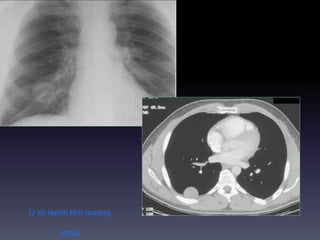

K thaäân di caên xs

K thaäân dicaên xs